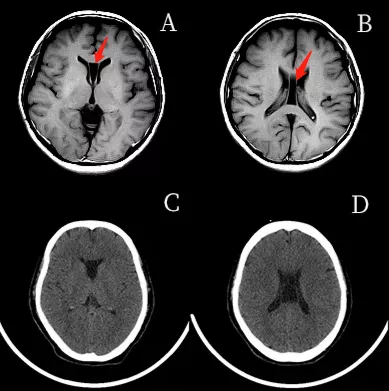

透明隔間腔是在顱內兩層透明隔之間形成的腔隙,它的上界為胼胝體體部,前下方為胼胝體膝部及嘴部和前聯合,底部和後方為穹窿。透明隔間腔被認為是人腦發育過程中的正常結構,通常在出生後的幾個月內閉合,但該結構亦存在於少數成人中。但是,將透明隔間腔稱為"第五腦室"是不正確的,因為它的內壁未襯有室管膜細胞,其內含有的液體也通常與腦室系統不同,因此透明隔間腔不具備腦室的組織結構特徵。

透明隔腔(CSP)的前上方為胼胝體,後下方為穹隆。側壁即透明隔小葉。透明隔腔≤3mm,描述可見透明隔腔。

透明隔腔增寬是透明隔腔≥3mm,直徑<10mm,描述可見透明隔腔增寬,透明隔的兩壁呈前後平行排列,邊界清晰,或內凹,對周圍組織無壓迫,為正常生理變異,臨床無症狀。透明隔腔≥10mm,描述可見透明隔腔明顯增寬。

兩壁呈前後內凹

兩壁呈前後平行